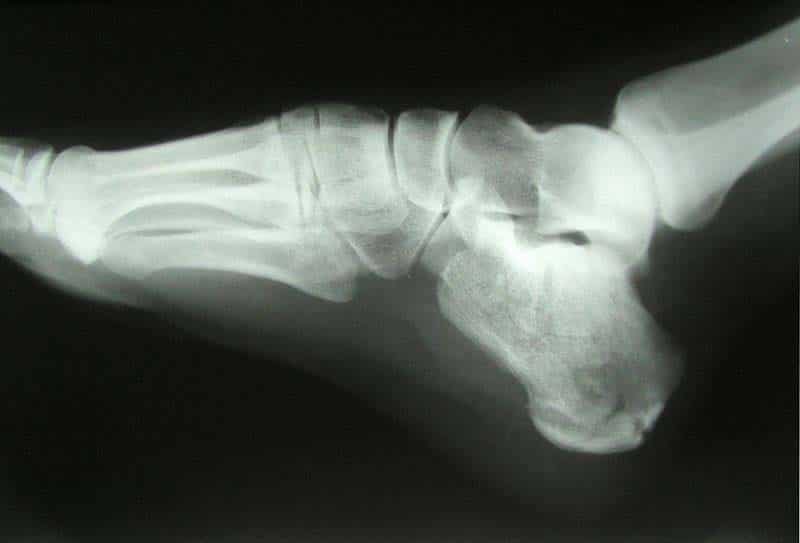

The bones of the foot provide mechanical support for the soft tissues; helping the foot withstand the weight of the body whilst standing and in motion. They can be divided into three groups: Tarsals – a set of seven irregularly shaped bones. They are situated proximally in the foot in the ankle area. Metatarsals – connect the phalanges to the tarsals. There are five in number – one for each digit. Phalanges – the bones of the toes. Each toe has three phalanges – proximal, intermediate, and distal (except the big toe, which only has two phalanges). The foot can also be divided up into three regions: (i) Hindfoot – talus and calcaneus; (ii) Midfoot – navicular, cuboid, and cuneiforms; and (iii) Forefoot – metatarsals and phalanges. In this article, we shall look at the anatomy of the bones of the foot – their bony landmarks, articulations, and clinical correlations. By TeachMeSeries Ltd (2025) Fig 1.0Overview of the bones of the human foot. Pro Feature - 3D Model You've Discovered a Pro Feature Access our 3D Model Library Explore, cut, dissect, annotate and manipulate our 3D models to visualise anatomy in a dynamic, interactive way. Learn More Tarsals The tarsal bones of the foot are organised into three rows: proximal, intermediate, and distal. Proximal Group The proximal tarsal bones are the talus and the calcaneus. These comprise the hindfoot, forming the bony framework around the proximal ankle and heel. Talus The talus is the most superior of the tarsal bones. It transmits the weight of the entire body to the foot. It has three articulations: Superiorly – ankle joint – between the talus and the bones of the leg (the tibia and fibula). Inferiorly – subtalar joint – between the talus and calcaneus. Anteriorly – talonavicular joint – between the talus and the navicular. The main function of the talus is to transmit forces from the tibia to the heel bone (known as the calcaneus). It is wider anteriorly compared to posteriorly which provides additional stability to the ankle. Whilst numerous ligaments attach to the talus, no muscles originate from or insert onto it. This means there is a high risk of avascular necrosis as the vascular supply is dependent on fascial structures. Calcaneus The calcaneus is the largest tarsal bone and lies underneath the talus where it constitutes the heel. It has two articulations: Superiorly – subtalar (talocalcaneal) joint – between the calcaneus and the talus. Anteriorly – calcaneocuboid joint – between the calcaneus and the cuboid. It protrudes posteriorly and takes the weight of the body as the heel hits the ground when walking. The posterior aspect of the calcaneus is marked by calcaneal tuberosity, to which the Achilles tendon attaches. By TeachMeSeries Ltd (2025) Fig 2The tarsal bones of the foot. Intermediate Group The intermediate row of tarsal bones contains one bone, the navicular (given its name because it is shaped like a boat). Positioned medially, it articulates with the talus posteriorly, all three cuneiform bones anteriorly, and the cuboid bone laterally. On the plantar surface of the navicular, there is a tuberosity for the attachment of part of the tibialis posterior tendon. Distal Group In the distal row, there are four tarsal bones – the cuboid and the three cuneiforms. These bones articulate with the metatarsals of the foot The cuboid is furthest lateral, lying anterior to the calcaneus and behind the fourth and fifth metatarsals. As its name suggests, it is cuboidal in shape. The inferior (plantar) surface of the cuboid is marked by a groove for the tendon of fibularis longus. The three cuneiforms (lateral, intermediate (or middle) and medial) are wedge shaped bones. They articulate with the navicular posteriorly, and the metatarsals anteriorly. The shape of the bones helps form a transverse arch across the foot. They are also the attachment point for several muscles: Medial cuneiform – tibialis anterior, (part of) tibialis posterior, and fibularis longus Lateral cuneiform – flexor hallucis brevis Clinical Relevance Fractures of the Talus and Calcaneus The talus and the calcaneus are primarily involved in transmitting forces from the body to the ground (and vice versa). This means they are frequently fractures in high-energy trauma. Talus Talar fractures most commonly occur in the neck region (50%), but can also occur in the body or lateral process. Fractures of the talar head are the least common. Talar neck fractures are typically high-energy injuries where the foot is forcibly dorsiflexed and the neck of the talus is pushed against the tibia. In this type of fracture, the blood supply to the talus may be disturbed – leading to avascular necrosis of the bone. Fractures of the talar body usually occur from jumping from a height. Calcaneus The calcaneus is often fractured as a result of axial loading, typically from a fall from a height. These patients should be assessed for associated injuries such as fractures of the lumbar spine or lower limb. The bone can break into several pieces (comminuted fracture). On x-ray, the calcaneus will appear shorter and wider. Even after treatment, a calcaneal fracture can cause further problems. The sub-talar joint is usually disrupted, causing the joint to become arthritic. The patient can experience pain upon inversion and eversion – which can make walking on uneven ground particularly painful. The calcaneo-cuboid joint can also be affected. By Jojo (Own work) [CC-BY-SA-3.0], via Wikimedia Commons Fig 3X-ray of a calcaneal fracture. Metatarsals The metatarsals are located in the forefoot, between the tarsals and phalanges. They are numbered I-V (medial to lateral). Each metatarsal has a similar structure. They are convex dorsally and consist of a head, neck, shaft, and base (distal to proximal). They have three or four articulations: Proximally – tarsometatarsal joints – between the metatarsal bases and the tarsal bones. Laterally – intermetatarsal joint(s) – between the metatarsal and the adjacent metatarsals. Distally – metatarsophalangeal joint – between the metatarsal head and the proximal phalanx. Clinical Relevance Fractures of the Metatarsal Bones Metatarsal fractures can occur by three main mechanisms. The most common method of fracture is a direct blow to the foot – usually from a heavy object dropping onto the foot. Another type of metatarsal injury is a stress fracture, an incomplete fracture caused by repeated stress to the bone. It is common in athletes and occurs most frequently at the necks of the second and third metatarsals and the proximal fifth metatarsal. The metatarsals can also be fractured by excessive inversion of the foot. If the foot is violently inverted, the fibularis brevis muscle can avulse (‘tear off’) the base of the fifth metatarsal. Phalanges The phalanges are the bones of the toes. The second to fifth toes all have proximal, middle, and distal phalanges. The great toe has only 2; proximal and distal phalanges. They are similar in structure to the metatarsals, each phalanx consists of a base, shaft, and head. Do you think you’re ready? Take the quiz below Pro Feature - Quiz Bones of the Foot: Tarsals, Metatarsals and Phalanges Question 1 of 3 Submitting... Skip Next Rate question: You scored 0% Skipped: 0/3 1800 More Questions Available Upgrade to TeachMeAnatomy Pro Challenge yourself with over 1800 multiple-choice questions to reinforce learning Learn More Rate This Article